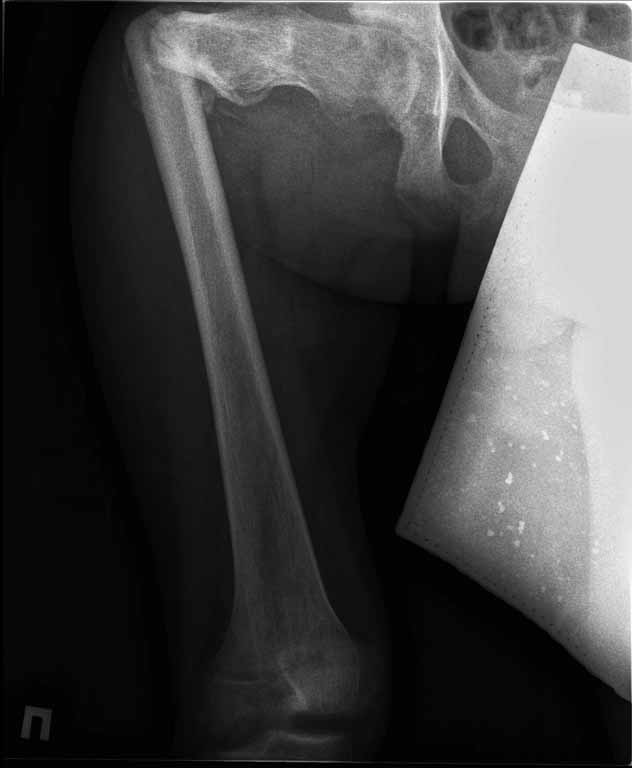

На лечении находится пациент с тяжелой сочетанной травмой. На сегодняшний день встал вопрос о тактике лечения переломов бедер( по месту жительства бедрами не занимались).

Пациенту 22 года. Травма в июле 2010г, лечился в районной больнице. К нам попал в апреле 2011г. Тяжелая сочетанная травма (29.07.2010): тупая травма живота с повреждением внутренних органов. Закрытая травма грудной клетки с переломом ребер. Пневмоторакс справа. Тяжёлая позвоночно-спинномозговая травма. Закрытый осложнённый переломо-вывих С5 позвонка. Верхний парапарез, нижняя параплегия, нарушение функции тазовых органов по типу недержания. Цекостома. Пролежень левой ягодичной области. Неправильно консолидированные переломы верхних третей обеих бедер. Застарелый вывих левого бедра. Осложнение: Поддиафрагамльный абсесс слева, забрюшинного пространства. Свищ желудка и ободочной кишки. Синегнойный сепсис. Двухстороняя пневмония. Но это уже анамнез. Пациент был неоднократно оперирован на органах брюшной полости и осложнениями с ними связанными.

В ягодичной области слева глубокий пролежень размером 2х2см, дном является вывихнутая головка бедра. Неврологически в нижних конечностях динамика положительная, появились движения в правой стопе, чувствительность в стопах. По переломам бедер: подвижности в местах переломов нет, снимки высылаю.

Уважаемые коллеги, помогите определиться с оптимальной тактикой в лечении перелома бедер. Степень оснащенности у нас достаточная (аппараты, штифты, пластины, ЭОП).

Планирую начать с правого бедра, ЧКО таза (передняя рама) с фиксацией бедра. О/клазия места перелома правого бедра и устранение грубых смещений в аппарате. окончательно можно оставить и в аппарате. Далее аппаратное устранение вывиха левого бедра.